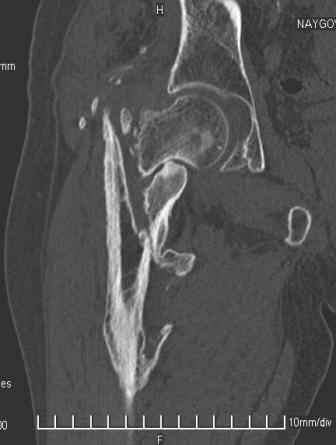

Больной Н. 44 года травма 1,5 года назад июнь 2008 года чрез-под вертельный перелом правого бедра. Во время лечения у больного развился алк. делирий, проводилось консервативное лечение перелома.

Беспокоят боли, укорочение конечности.Укорочение 3 см. Ногу поднимает, сгибание ограничено, ротационные движения в полном объеме.На КТ перелом сросся за счет костной мозоли.Что делать?

Протез? Если «да» Можно ли обойтись стандартной ножкой Corail?

Или межвертельная остеотомия?

Уважаемый Глеб, боли из-за ложного сустава шейки бедра. Сращения там нет.

Тазобедренный сустав сохранный и возраст пациента позволяет побороться. Согласен с Максимом, попробуйте остеотостеотомию.

Уважаемый Глеб! Укорочение наверное побольше, да и наружно-ротационная установка скорее всего присутствует. Суставная щель прекрасная, головка живее всех живых. Ратую за подвертельную с латерализацией: исключает нарушение механической оси («исключает вальгус в коленe»), максимально удлиняет без натяжения m.iliacus. Для иллюстрации остеотомия-переделка (слава богу не автопеределка) у мужчины 65 лет.